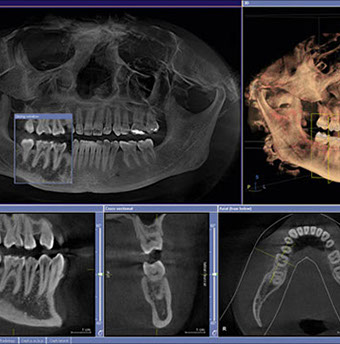

Si rilevano delle impronte e si eseguono della radiografie, normalmente una CBCT (Vedere sezione Imaging & Diagnostica) per definire la fattibilità dell’intervento e per programmarne la realizzazione.